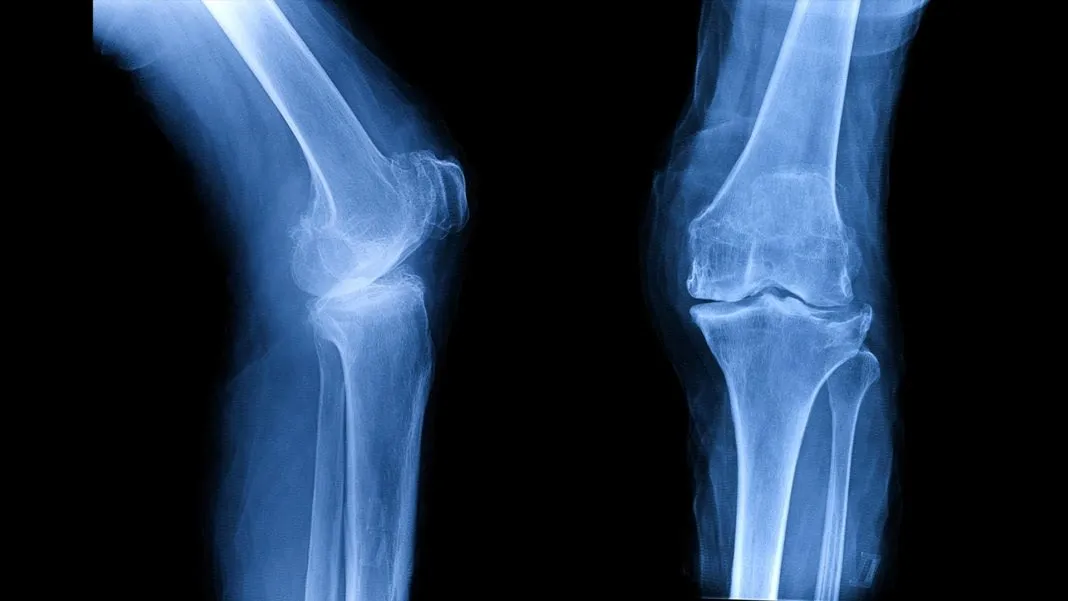

Tandon’s expertise, though, is in personalized bones (not a term you ever thought you’d hear, is it?). “Bone is the most transplanted human tissue after blood,” she said. “And we’re replacing over a million joints every year in this country alone, just because of a couple millimeters of damaged cartilage. Welcome to the hundred-billion-dollar medical device industry.”

Then, around the turn of the last century, we started developing interchangeable parts (whether from donors, or made of plastic or metal), and thinking of our bodies a bit more like machines. “We’re each made out of 206 bones held together by 360 joints,” Tandon said. “But many of us are more than that. By the time we go through this lifetime, 70 percent of us will be living with parts of our body that we weren’t born with.”

If that percentage seems high—it did to me—consider all the things that count as ‘parts’ of our bodies that are artificial: Dental implants. Pacemakers. IUDs. Joint replacements.